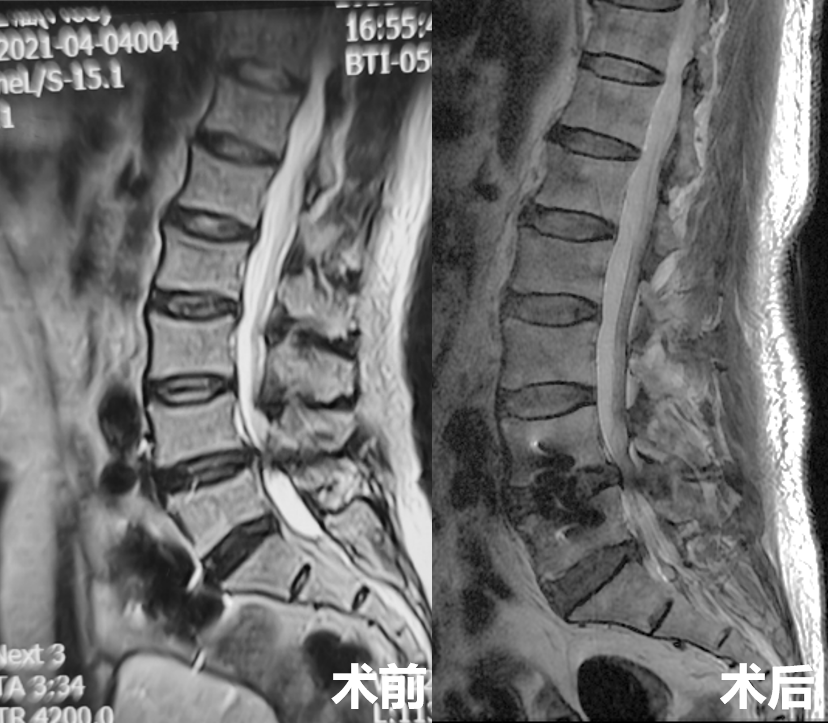

术后复查

第三例51岁女性患者,因“右下肢放射性疼痛、麻木1年,加重1月余”入院,发病以来反复多次保守治疗无效。入院后经术前讨论、评估,制定治疗方案,行OLIF手术,该病例采用后路经皮椎弓根螺钉内固定。次日患者下地活动,下肢症状消失,疗效满意。

术前影像